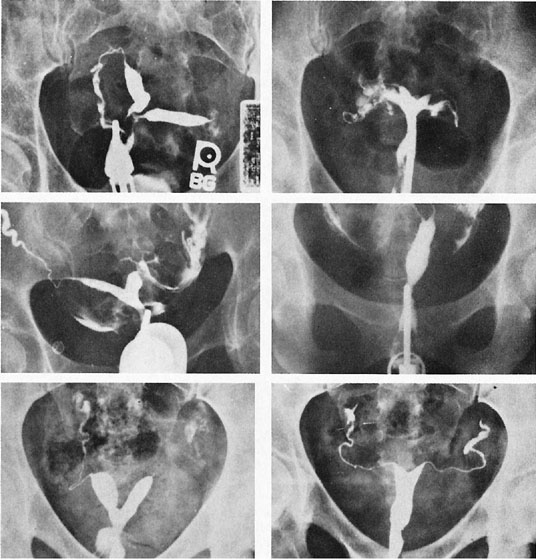

The unique clinical syndrome of double uterus, unilateral partial or complete obstruction of the vagina, and ipsilateral renal aplasia is rare (Fig. 14; see Fig. 13). The clinical presentation varies depending on the uterovaginal relationships, which may obscure the true diagnosis. Three groups of patients have emerged from a review of our own experience (Table 7).29 Group 1 consists of patients with a complete unilateral vaginal obstruction without uterine communication, which results in a perivaginal mass with severe dysmenorrhea, lower abdominal pain, and regular menses. Group 2 consists of patients with incomplete unilateral vaginal obstruction without uterine communication. These patients have lower abdominal pain, severe dysmenorrhea, excessive foul mucopurulent discharge, and intermenstrual bleeding. Group 3 patients have complete vaginal obstruction with a laterally communicating double uterus. They have a perivaginal mass, lower abdominal pain, dysmenorrhea, and regular menses. Irregular menstrual bleeding usually confuses the physician such that unless she or he thinks of the possibility of the diagnosis, the diagnosis may be overlooked. A hysterogram, intravenous pyelogram, and careful pelvic examination often allow the diagnosis to be made. When there is complete unilateral obstruction, a large amount of blood may accumulate, and this condition may go unrecognized for a number of years after the onset of menstruation. This is due primarily to a distensible vagina that can accommodate to the increments of blood resulting from each menstrual cycle. Absorption of enough menstrual blood occurs between periods so that succeeding flow may add to the accumulated blood without pain. Nevertheless, once retrograde menstruation occurs, endometriosis invariably results. Thus, if the septum may be removed before the tubes and ovaries are compromised by infection or endometriosis, reproduction may be consistent with uterine duplication without obstruction.

Fig. 14. Double uterus, complete or incomplete vaginal obstruction, and ipsilateral renal agenesis. A. Complete vaginal obstruction. B. Incomplete vaginal obstruction. C. Complete vaginal obstruction with a lateral communicating double uterus.(Rock JA, Jones HW Jr: The double uterus associated with an obstructed hemivagina and ipsilateral renal agenesis. Am J Obstet Gynecol 138:340, 1980)

Rarely, a situation exists in which a low vaginal obstruction is associated with a lateral communication between the two horns of the uterus (see Fig. 14C). Patients may complain of a disappearing mass at the vaginal outlet. A careful hysterogram under fluoroscopy is often useful in identifying the communication.